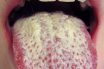

Candidiasis (thrush)

An infection caused by the fungus genus Candida. It is associated with multiple influencing factors that include (a) the use of broad‐spectrum antibiotics, (b) diabetes mellitus, (c) xerostomia, (d) suppression of the immune system, and (e) pregnancy. Clinically, it appears as soft, white, curd‐like plaques that can be wiped off, leaving an erythematous area.